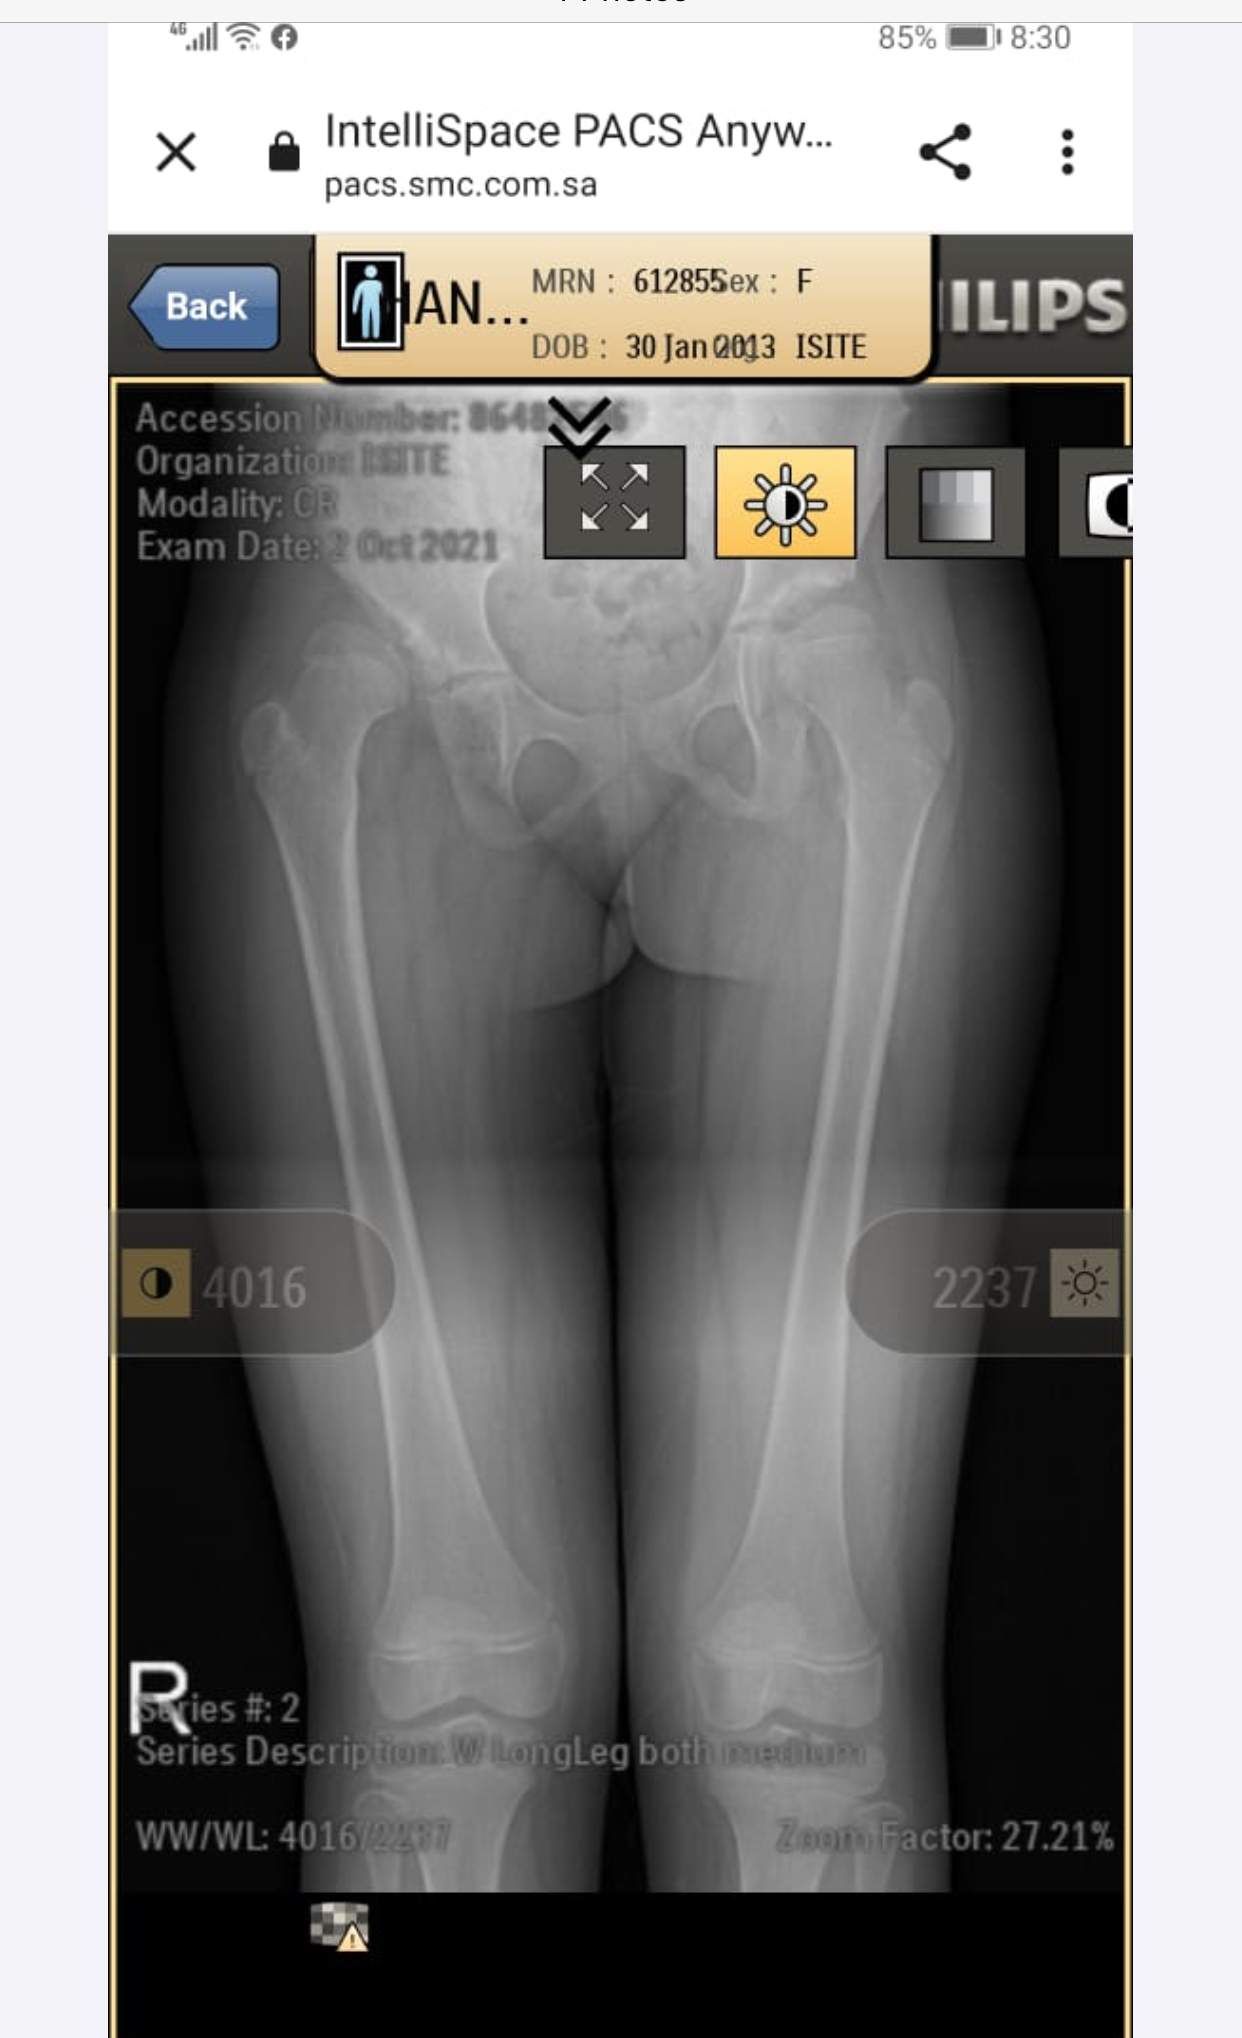

My daughter is diagnosed with hip dysplasia at age of 8.8 years. Doctor is saying for surgery immediately but we got another opinion and that surgeon is saying that there is no success rate of surgery right now. You have to wait once she grow up n then we will go for hip replacement. While the other doctor is saying that surgery is must. We need an opinion on it. Xrays are attached

she definitely need surgery to keep the head at level of socket. you should consult DR. CHIRAGH at GHURKI TRUST HOSPITAL, LAHORE. He is very experienced and expert for this disease.

it needs operation as soon as possible.

Surgery at present at 9yrs of age won't result good results. And re-dislocation may occur soon after surgery. Wait for maturity and then go for translational osteotony/replacement surgery.

Salam, She needs to get MRI of hip joint to measure angles related to hip dysplasia and clinical exam as well before deciding surgery. Thanks